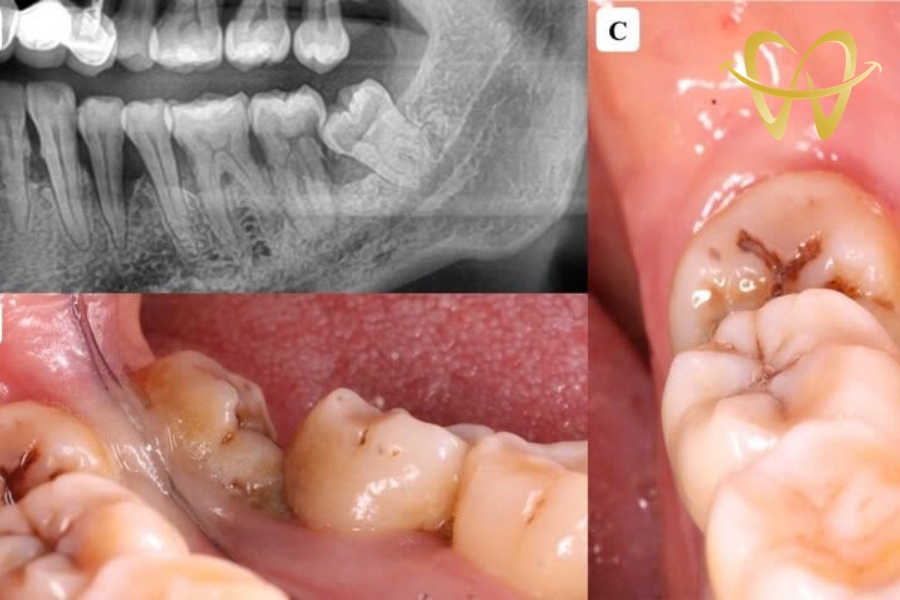

Đến nha sĩ để chụp CT kiểm tra

Cách chính xác nhất để xác định răng khôn mọc lệch là chụp CT. Hình ảnh sẽ cho thấy hướng mọc, độ nghiêng và mức độ ảnh hưởng đến răng bên cạnh. Từ đó, bác sĩ sẽ tư vấn nên giữ hay nhổ bỏ. Việc chụp CT còn giúp phát hiện sớm những răng khôn mọc ngầm hoặc mọc lệch nhẹ. Điều này giúp bạn có kế hoạch xử lý trước khi cơn đau trở nên nghiêm trọng.